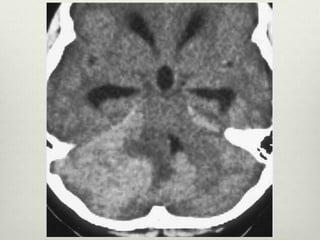

Tomografía

• Hiperdensa , bien definida vermiana o en hemisferio

cerebeloso

• Edema vasogénico

• Compresion IV Ventriculo

• Evidencia de la hidrocefalia

• Realce de contraste homogéneo

• La formación de quistes ( 59 % de los

casos)

• La calcificación - infrecuente

Tomografía • Hiperdensa ,bien definida vermiana o en hemisferio cerebeloso • Edema vasogénico • Compresion IV Ventriculo • Evidencia de la hidrocefalia • Realce de contraste homogéneo • La formación de quistes ( 59 % de los casos) • La calcificación - infrecuente